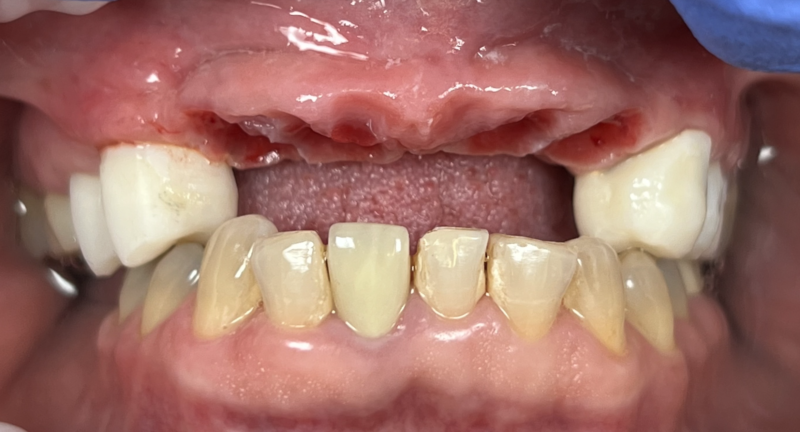

Ivan posted an update 2 years ago

I want to share a case I’m particularly proud of. My homie AJ Marbeh in San Diego took this case from start to finish. After taking the online GBR course by David Wong he crushed it with this difficult case and he used Implant Club fixtures. Brings a tear of happiness to my eye. LOL but seriously, Love this case!